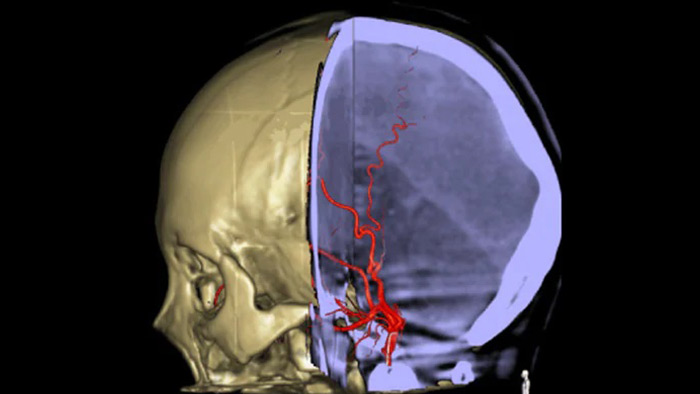

SmartCT Soft Tissue  genera una visualización similar a la de un TAC convencional de tejido blando y respalda el diagnóstico de accidentes cerebrovasculares de tres maneras. Una exploración sin contraste ayuda a la detección de cambios isquémicos tempranos. Una exploración en fase temprana ayuda a identificar la oclusión proximal. Una exploración con contraste en fase tardía respalda la detección de colaterales.

SmartCT Vaso IV

Compruebe la ubicación y la longitud de un coágulo

SmartCT Vaso permite la visualización más allá del coágulo con la adquisición de imágenes periprocedimiento de los aspectos del vaso distal en el accidente cerebrovascular isquémico. SmartCT Vaso es una técnica de adquisición basada en una exploración por TAC de haz cónico y una inyección de contraste intraarterial. Mediante la repleción retrógrada, las estructuras de los vasos antes y después del coágulo se vuelven visibles. Además, SmartCT Vaso 3D Roadmap puede utilizarse para visualizar dispositivos de recuperación de coágulos.